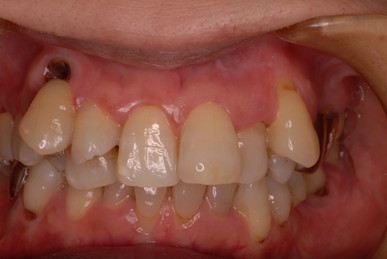

下の写真の方は虫歯と歯の間の歯周病が酷かったのです。

虫歯の治療も完全にできませんし、歯の位置が悪く又重なっている為に歯周病が治らずに説得に数カ月を有した後に矯正することになりました。

矯正は簡単なのですが、虫歯や歯周病にならないように、又かみ合わせや関節、筋肉に問題を起こさないように矯正するのは難しいのです。